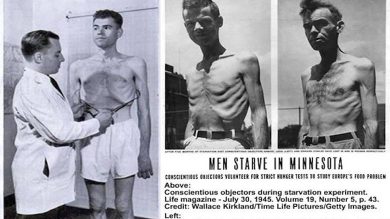

Minnesota Açlık Deneyi Açlık Hakkında Bize Ne Öğretti?

Aşırı açlık insanları nasıl etkiler? Günümüzde bu sorunun cevabını Minnesota Açlık Deneyi sayesinde biliyoruz. Ancel Keys adı günümüzde daha çok…